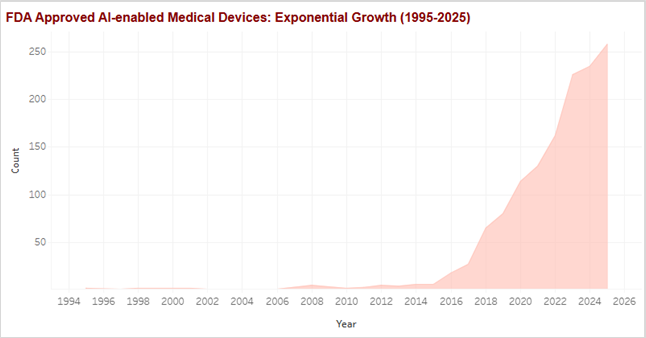

Figure 2: FDA-Approved AI-Enabled Medical Devices Trend – Exponential growth acceleration post-2018.

Early activity concentrated heavily in radiology, which served as the initial proving ground. That concentration is visible in sustained growth from the mid-2010s onward, establishing radiology as the foundation layer for clinical AI adoption. More importantly, this early success unlocked confidence, regulatoryprecedent, and workflow acceptance that would later enable expansion beyond imaging.

During the initial deployment phase between 2015 and 2022, these technologies functioned as isolated applications identifying specific pathologies within constrained domains. The current generation represents a qualitative departure. Advanced generative architectures now synthesize disparate data modalities (diagnostic imaging, genetic sequencing, longitudinal health records) into unified stratification frameworks, moving beyond detection toward comprehensive risk interpretation.